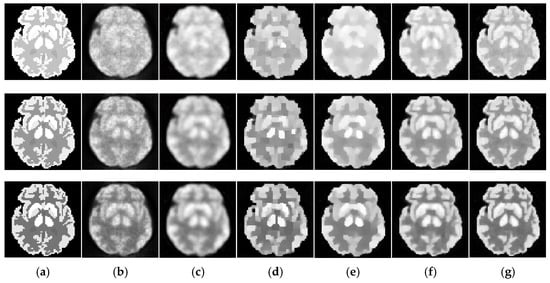

Figure 6.

Dynamic brain phantom reconstructed by different algorithms. The total photon counts are over 18 image frames. From the first to the last row: the 5th, 11th and 17th frame. (a) ground truth, (b) ML-EM (16.01 dB, 16.41 dB, 15.92 dB), (c) PWLS (17.71dB, 16.88dB, 16.23dB), (d) TV-AL (18.49 dB, 18.76 dB, 18.52 dB), (e) PLH-IO (21.26 dB, 19.56 dB, 18.39 dB), (f) ST-TV (21.27 dB, 20.59 dB, 19.02 dB), (g) Ours (21.79 dB, 21.71 dB, 20.63 dB).

The initial experiment focuses on the resolution and the denoising performance throughout the temporal dimension. According to the TAC in Figure 4, the distinction of activity between different ROIs is inconspicuous in the early imaging stage, which consequently hampers the recovery of the structural information in the corresponding image frames. As demonstrated in Figure 6, the reconstructions of ML-EM and PWLS suffer from severe iterative noise and fail to recover a clear boundary between regions. On the other hand, the TV-AL and PLH-IO show more acceptable results for the 17th frame. However, when it comes to former frames, neither of these two methods are able to recover clear structures. Moreover, the TV-AL suffers from the staircase effect and artifacts, and PLH-IO tends to over-smooth the image. Although ST-TV improves the resolution by incorporating temporal information, it is still limited by recovering more detailed structures. In contrast, our proposed method manages to recover more detailed structures and less noise in reconstructing the brain phantom sequence under photon counts. This contrast is more distinctive in simulated low-dose images. As we can see in Figure 7, when recovering early frames in the low-count data, our proposed method is able to recover substantially clearer structures than those of other methods under similar noise levels.